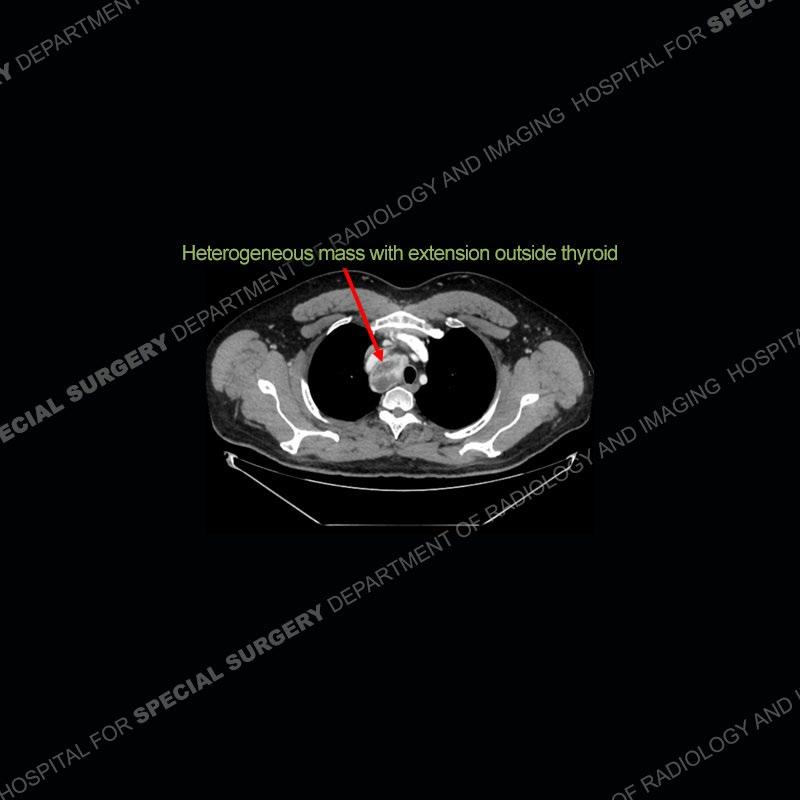

The chest radiographs demonstrate a leftward deviation of the trachea. CT images demonstrate a large, somewhat heterogeneous mass of the thyroid that extends outside the confines of the thyroid tissue. There is a subtle, enhancing soft tissue mass of the proximal right humerus. Slightly prominent mediastinal lymph nodes are present with additionally, multiple supraclavicular lymph nodes.

Over the years we have shown a couple of these cases which may be considered more so an “eye test” then anything else. In clinical practice, these are often very difficult cases as the initial finding of the tracheal deviation may be easily overlooked. Screening radiographs are clearly most often used to assess cardiopulmonary function before induction of anesthesia but at times other findings of great and unfortunately grave consequence can be found. The evaluation of the incidental thyroid mass on CT and MRI is an ever changing situation. Parameters such as age of patient, extension outside of the thyroid, enhancing nodules, and local invasion of lymph nodes are evaluated to see if a lesion needs to be further evaluated.

Although not strictly a part of the evaluation of an “incidental” thyroid lesion, evaluation of the adjacent lymph nodes and bony structures can also be quite important. In this case, there is an enhancing mass of the right humerus. This is very subtle and can only really be recognized by evaluating the density of the bone. Typicaly marrow will have a fatty density or nearly fluid density. As the density, as in this case, approaches soft tissue an infiltrative process must be entertained. Thyroid mets are markedly vascular accounting for the areas of enhancement of the humeral mass. The mediastinal and supraclavicular lymph nodes although not individually enlarged, should raise suspicion of an underlying inflammatory/neoplastic process.